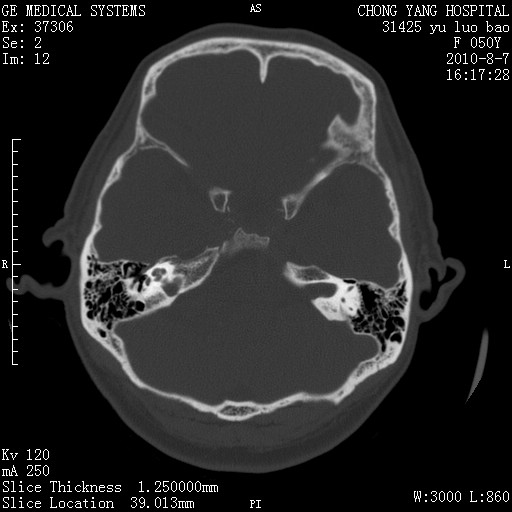

标题: CT28285:听力下降一年,头昏。 [打印本页]

标题: CT28285:听力下降一年,头昏。

右侧桥小脑角去等密度占位,右侧内听道扩大、骨质吸收,考虑:右侧听神经瘤,建议增强检查。

骨窗示右侧内听道扩大,考虑右侧听神经瘤。

右侧桥小脑角区等密度占位,内耳道扩大,听神经瘤